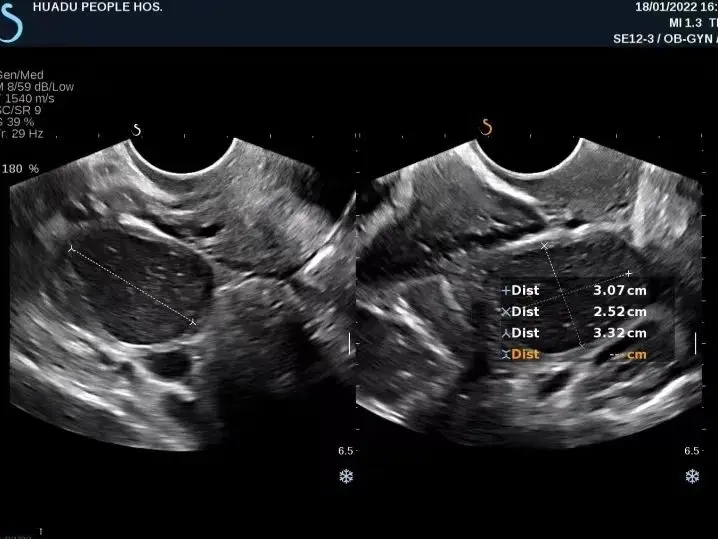

2. 囊肿大小: 囊肿大小也会对囊肿引流时间产生影响。较小的囊肿(直径小于2 cm)一般可以在短时间内引流出来,如24小时内。而较大的囊肿,特别是病灶较深或者囊壁较厚的囊肿,则可能需要更长时间进行引流。